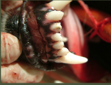

What is going on in these two images?

What is going on in these 2 images of closed extraction step 2?

What can be seen with the black and tranparent instrument?

What does a black dot mean on the tooth?

Exposed necrotic pulp